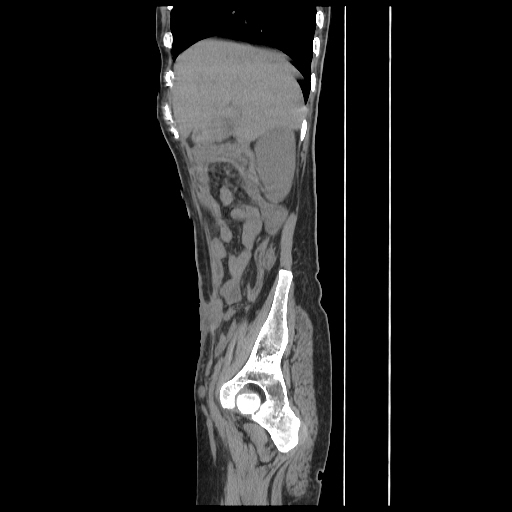

Radiological images:

CT-Scan investigation done on 16Apr16